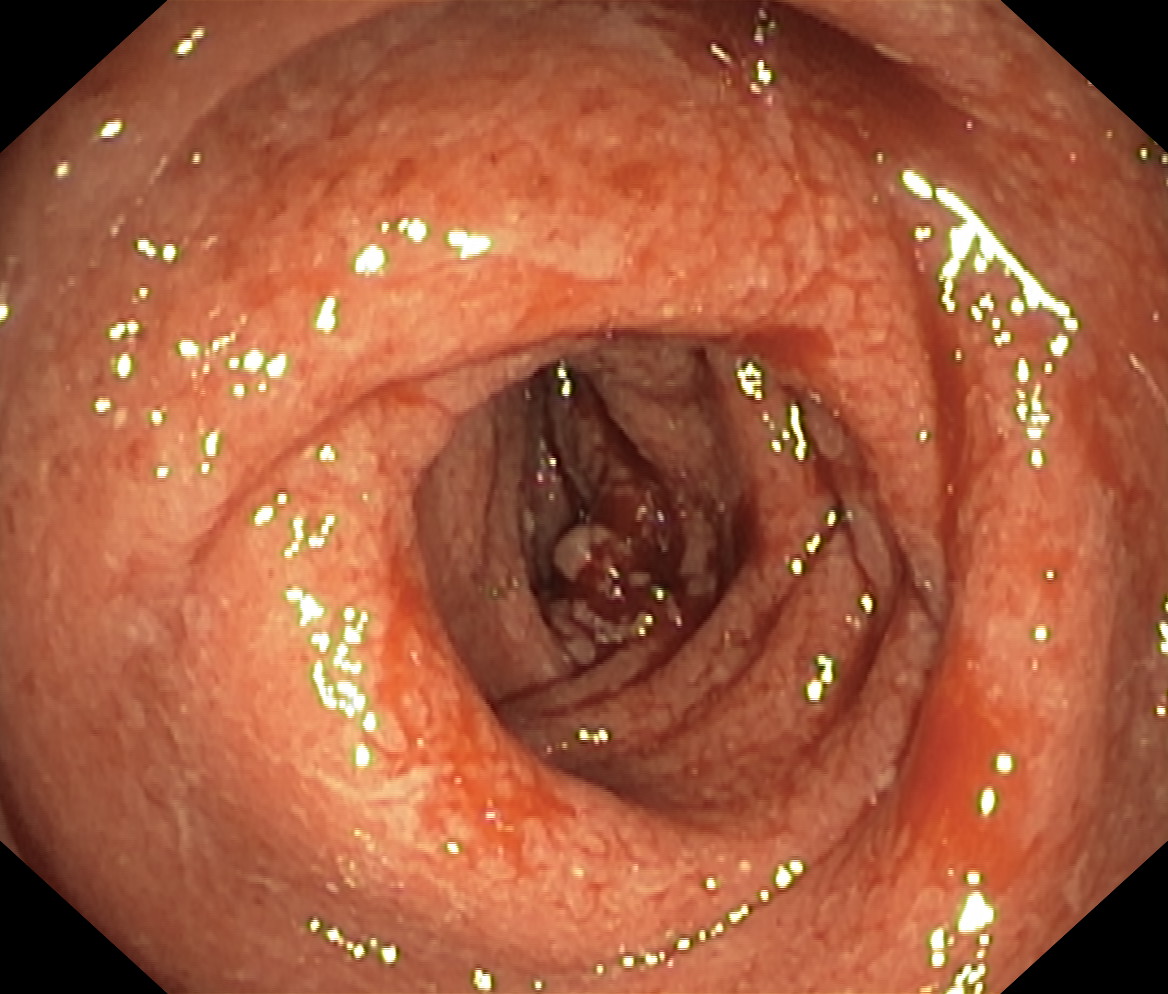

Zapalenie wrzodziejące...

Zapalenie wrzodziejące jelita grubego